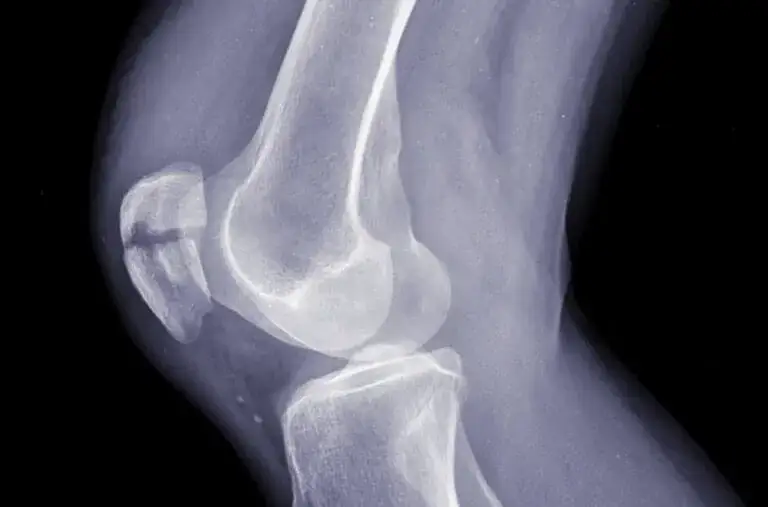

- Diagnostyka urazów kolana często wymaga badań obrazowych, takich jak rezonans magnetyczny czy tomografia komputerowa.

Diagnozowanie urazów kolana przez specjalistów zazwyczaj rozpoczyna się od dokładnego wywiadu medycznego i badania fizykalnego. Lekarz ocenia zakres ruchu, siłę mięśni oraz obecność obrzęku. W przypadku podejrzenia poważniejszych uszkodzeń, takich jak zerwanie więzadeł, mogą być konieczne badania obrazowe. Najczęściej stosowane metody to rezonans magnetyczny (MRI), który pozwala na dokładną ocenę tkanek miękkich, oraz rentgen, który sprawdza ewentualne złamania. Te diagnostyczne podejścia pomagają w ustaleniu odpowiedniego planu leczenia i rehabilitacji.

| Typ badania | Cel |

| Rezonans magnetyczny (MRI) | Ocena tkanek miękkich, więzadeł i ścięgien |

| Rentgen | Wykrywanie złamań kości |